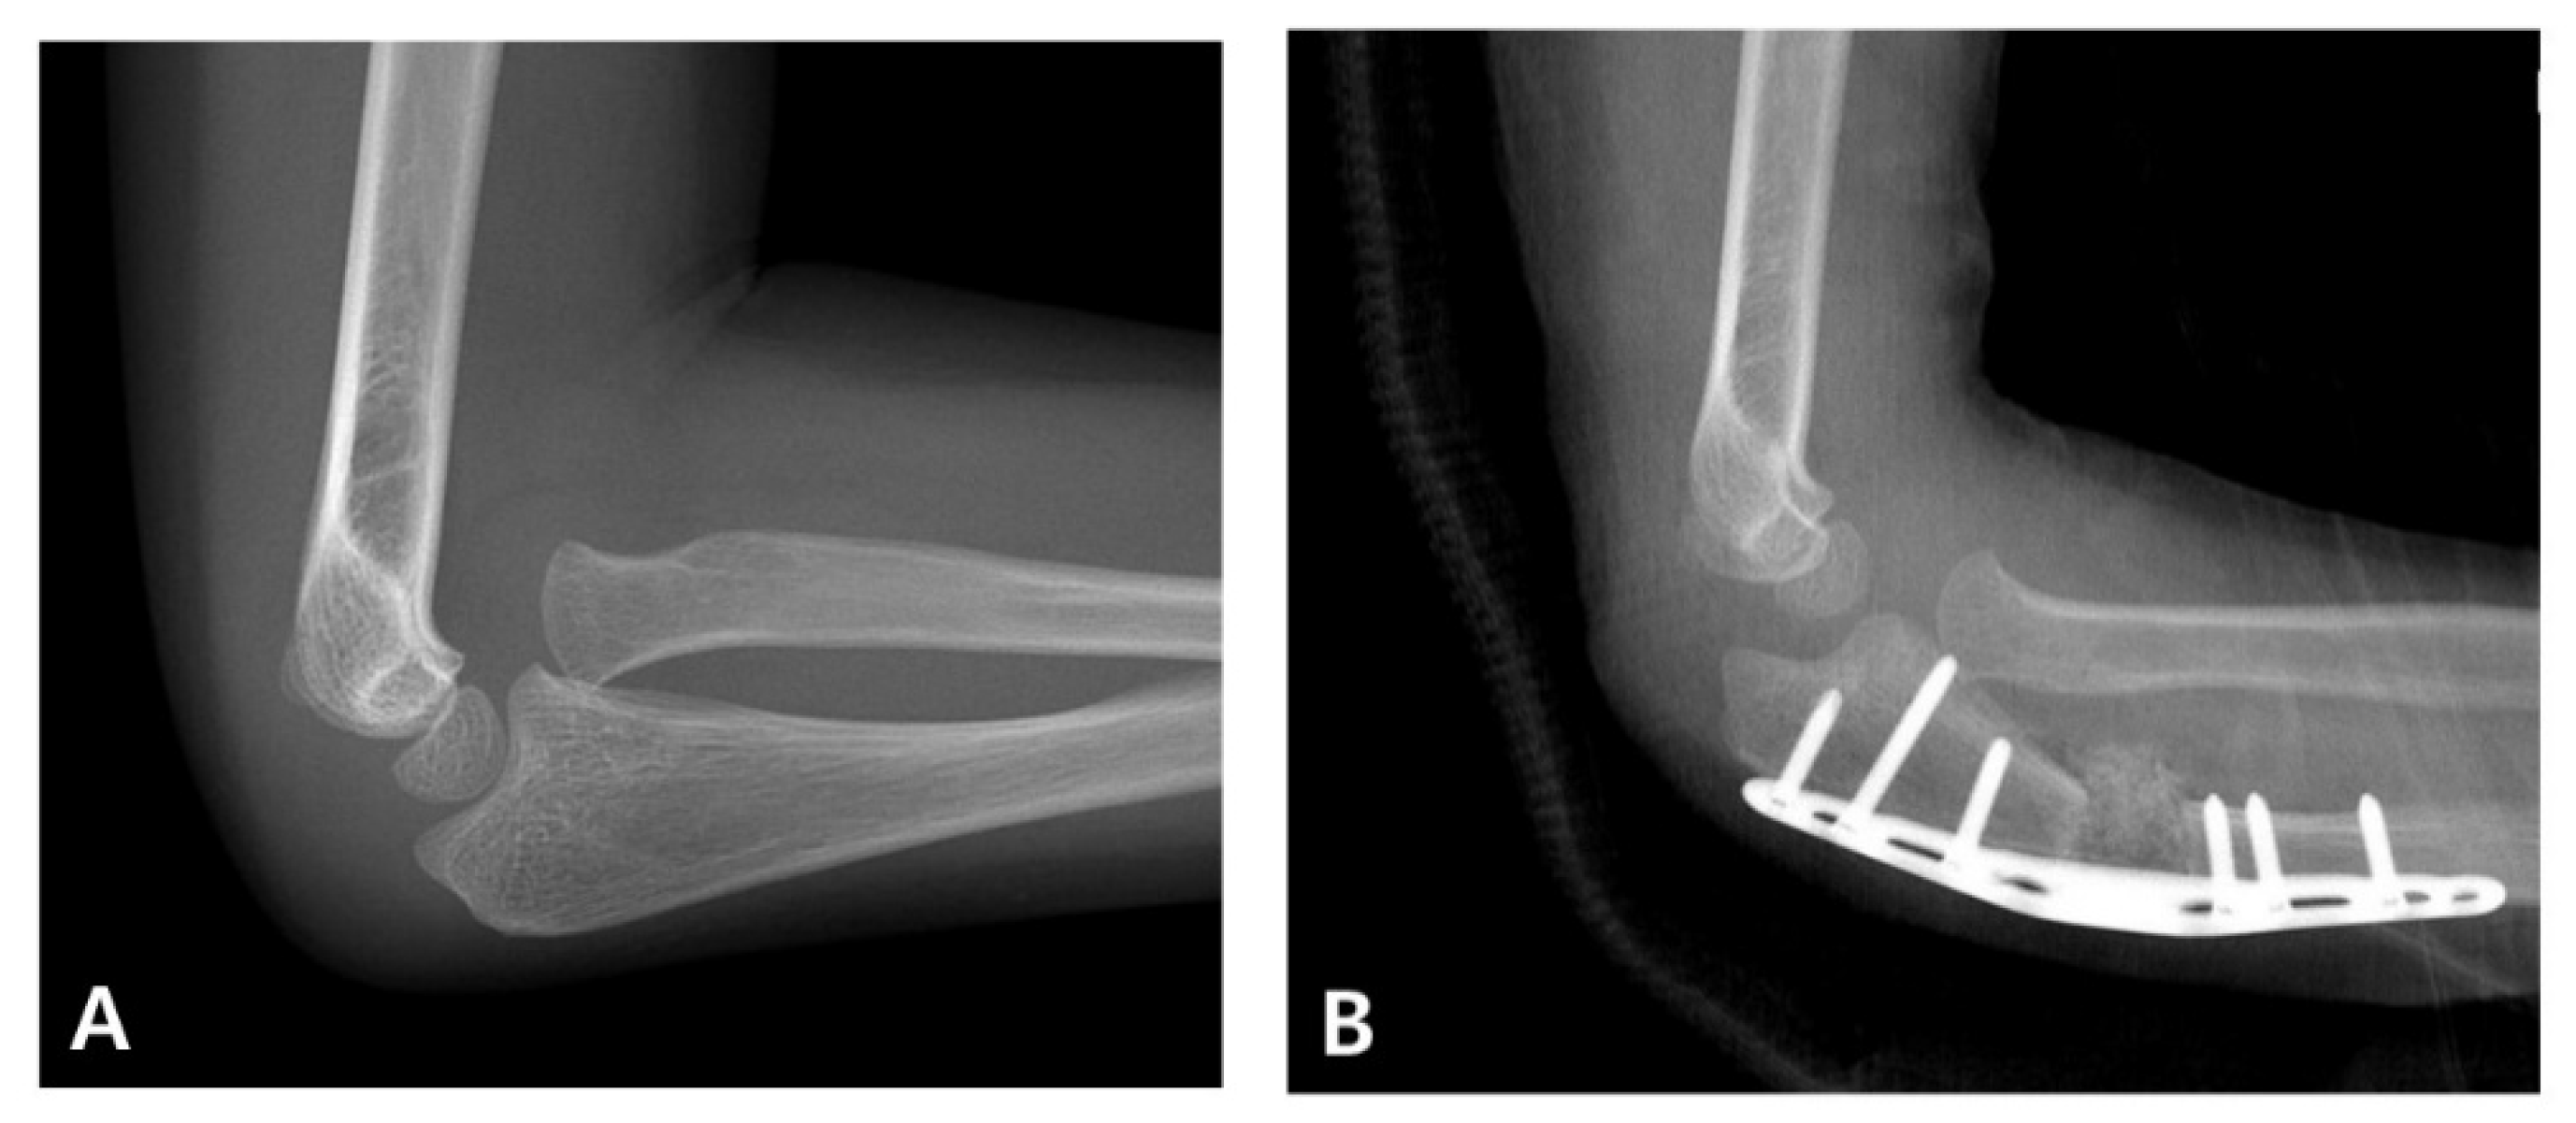

When diagnosis is delayed beyond the acute phase, the injury is considered a “neglected Monteggia fracture,” typically defined as untreated for more than two weeks. As illustrated in Figure 2, delayed treatment can result in chronic dislocation of the radial head, leading to progressive pain, valgus deformities, and a restricted range of motion [2,7]. Irreducibility due to soft tissue contracture or annular ligament entrapment may develop over time, and altered joint mechanics can result in degenerative changes and ulnar nerve dysfunction [2,8]. Surgical reconstruction (Figure 3), often involving ulnar osteotomy, open reduction, and annular ligament reconstruction, is necessary; however, the outcomes are generally inferior to those achieved with early intervention [2,9].

Figure 3. Surgical correction of a neglected Monteggia fracture-dislocation. (A) Preoperative radiographs of a 5-year-old boy showing persistent anterior dislocation of the radial head due to a previously unrecognized Monteggia lesion. (B) The patient underwent corrective ulnar osteotomy and open reduction surgery. Postoperative imaging confirmed the successful reduction and restoration of the radiocapitellar alignment.